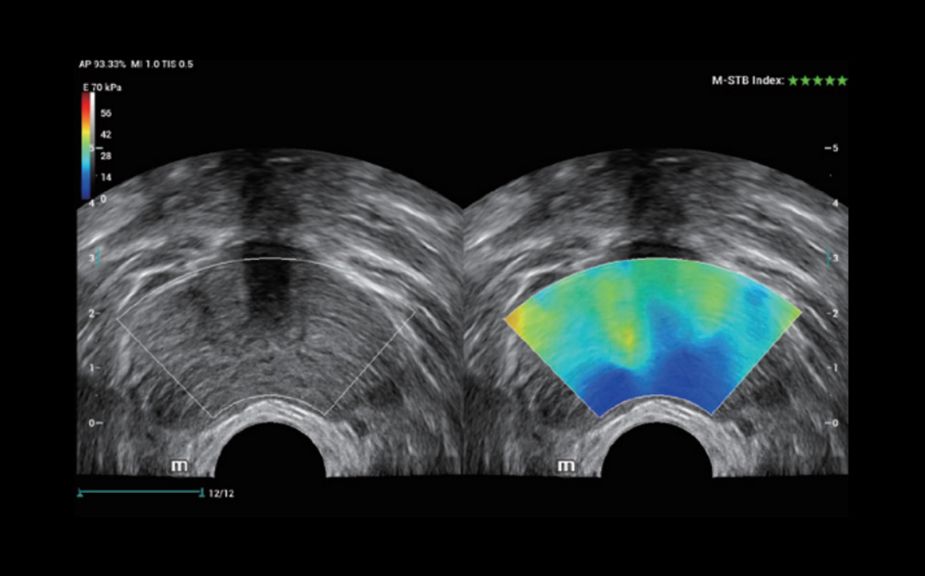

–ė–Ĺ–Ĺ–ĺ–≤–į—Ü–ł–ĺ–Ĺ–Ĺ–į—Ź –ĺ—Ü–Ķ–Ĺ–ļ–į –∂–Ķ—Ā—ā–ļ–ĺ—Ā—ā–ł: HiFR STE

–í 10 —Ä–į–∑ –Ī–ĺ–Ľ–Ķ–Ķ –≤—č—Ā–ĺ–ļ–į—Ź —á–į—Ā—ā–ĺ—ā–į –ļ–į–ī—Ä–ĺ–≤ –Ņ—Ä–ł —Ä–į–Ī–ĺ—ā–Ķ —Ä–Ķ–∂–ł–ľ–į STE

–í—č—Ā–ĺ–ļ–į—Ź —á—É–≤—Ā—ā–≤–ł—ā–Ķ–Ľ—Ć–Ĺ–ĺ—Ā—ā—Ć –ļ –ī–≤–ł–∂–Ķ–Ĺ–ł—é –ī–Ľ—Ź –Ņ–ĺ–≤—č—ą–Ķ–Ĺ–ł—Ź —Ā—ā–į–Ī–ł–Ľ—Ć–Ĺ–ĺ—Ā—ā–ł –ł —ā–ĺ—á–Ĺ–ĺ—Ā—ā–ł

–ė–Ĺ–Ĺ–ĺ–≤–į—Ü–ł–ĺ–Ĺ–Ĺ–į—Ź –ĺ—Ü–Ķ–Ĺ–ļ–į –∂–Ķ—Ā—ā–ļ–ĺ—Ā—ā–ł: HiFR STE

–í 10 —Ä–į–∑ –Ī–ĺ–Ľ–Ķ–Ķ –≤—č—Ā–ĺ–ļ–į—Ź —á–į—Ā—ā–ĺ—ā–į –ļ–į–ī—Ä–ĺ–≤ –Ņ—Ä–ł —Ä–į–Ī–ĺ—ā–Ķ —Ä–Ķ–∂–ł–ľ–į STE

–í—č—Ā–ĺ–ļ–į—Ź —á—É–≤—Ā—ā–≤–ł—ā–Ķ–Ľ—Ć–Ĺ–ĺ—Ā—ā—Ć –ļ –ī–≤–ł–∂–Ķ–Ĺ–ł—é –ī–Ľ—Ź –Ņ–ĺ–≤—č—ą–Ķ–Ĺ–ł—Ź —Ā—ā–į–Ī–ł–Ľ—Ć–Ĺ–ĺ—Ā—ā–ł –ł —ā–ĺ—á–Ĺ–ĺ—Ā—ā–ł